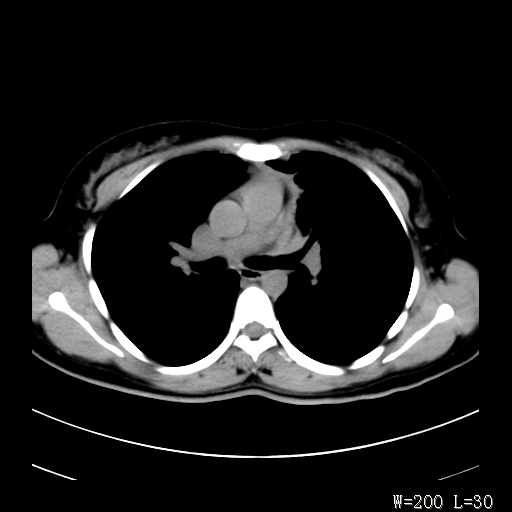

标题: CT27017:1、肺结核?2、永存左上腔静脉。 [打印本页]

标题: CT27017:1、肺结核?2、永存左上腔静脉。

女,32岁,自述肺结核治疗多年复查。

1)考虑左肺上叶肺脓肿,节段性肺不张。2)永存左上腔静脉。

1)考虑左肺上叶节段性肺不张。原因?2)永存左上腔静脉。

支持肺脓肿;还是双上腔静脉确切些吧,回流至冠状窦或右心房。

考虑左肺上叶胸腺瘤可能性大。肺不张/永存左上腔静脉

胸骨后偏左侧囊实性病灶,考虑胸腺瘤可能性大.

1、胸骨后偏左侧囊实性病灶,考虑胸腺瘤可能性大。2、永存左上腔静脉。